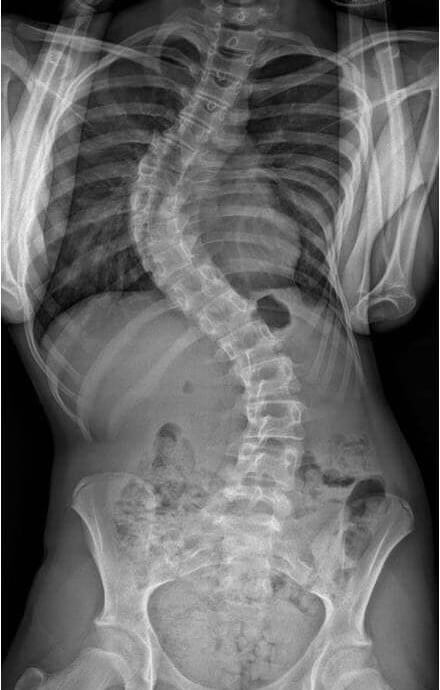

The full body, weight bearing scan enables accurate assessment of skeletal issues, including postural analysis, degree of scoliosis, leg length discrepancies and predisposition to spine disc disease.

It allows rapid imaging of the entire skeleton in a sitting or standing position at an extremely low radiation dose; making it the optimal orthopaedic imaging technology for monitoring spinal and skeletal conditions.